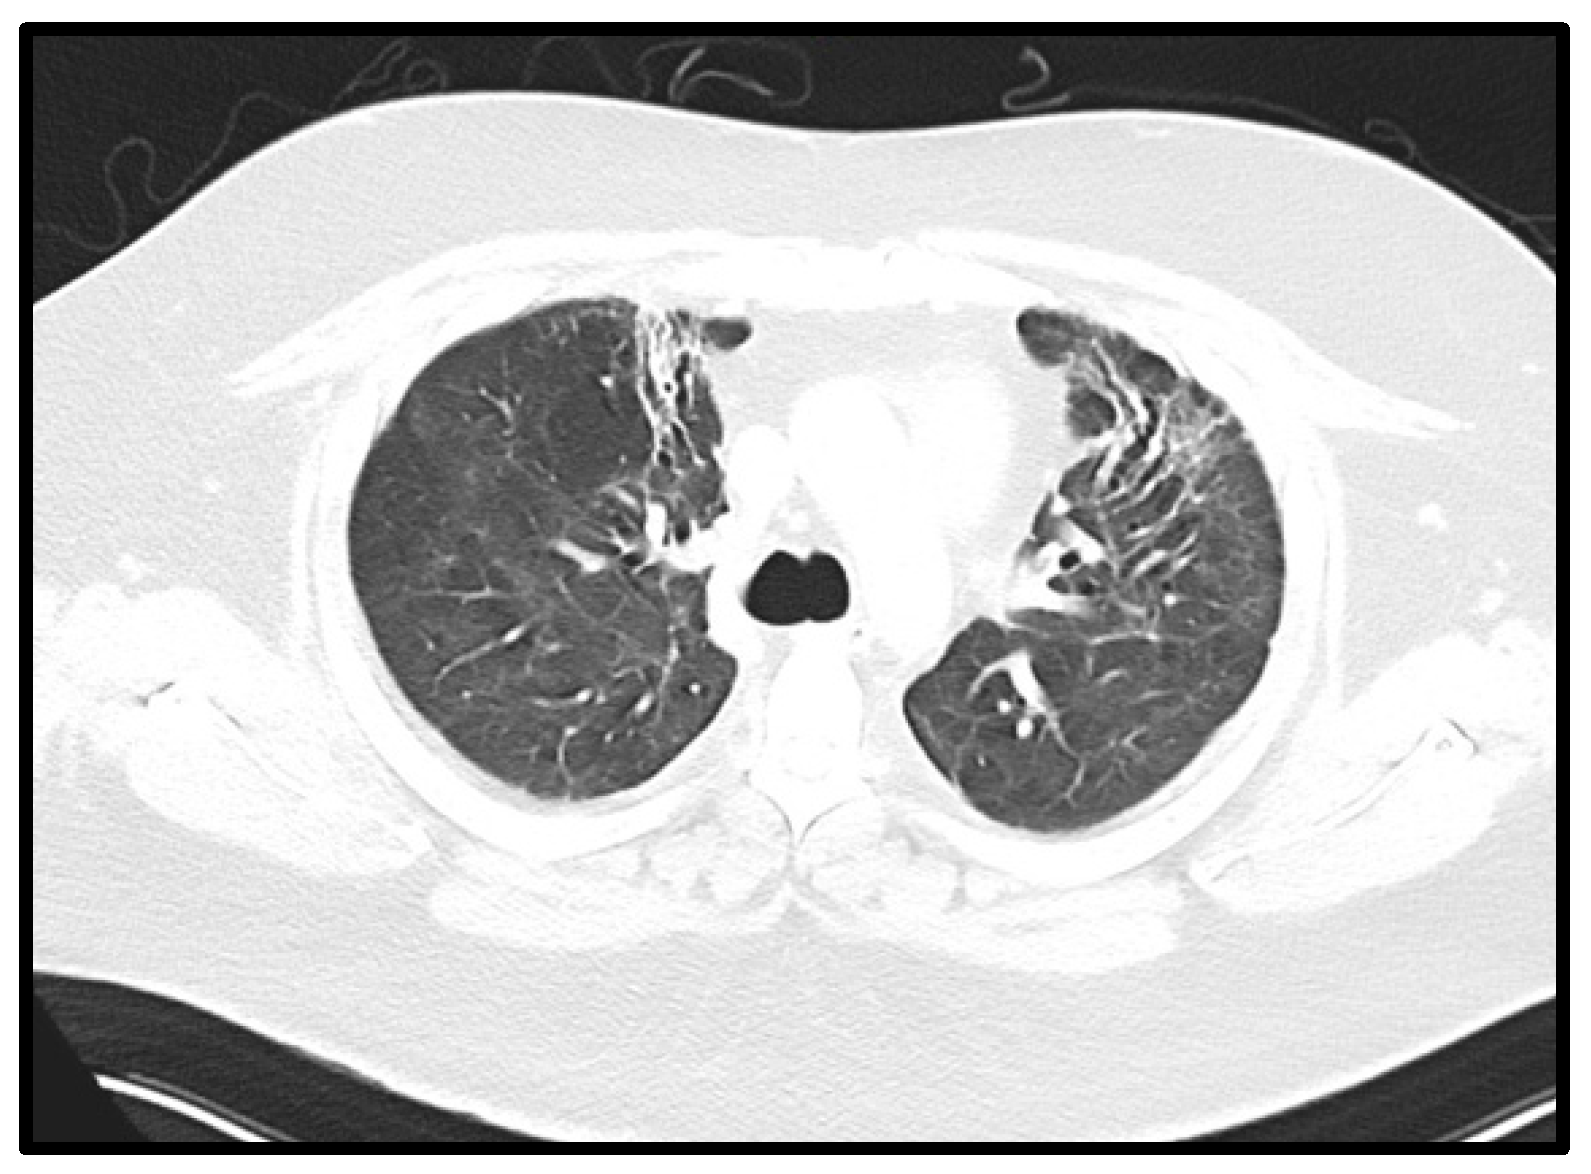

Figure 4.

Fibrotic changes in pulmonary CT. Axial CT of the chest performed 31 weeks after onset of symptoms showing reticular abnormalities and traction bronchiectasis in both anterior upper lobes, compatible with post-ARDS lung fibrosis.

The patient was continuously in care at Vienna General Hospital due to pulmonary and non-pulmonary complications after his long-term ICU stay (Table 2). The patient received two additional cycles of cyclophosphamide and high-dose steroids, which were generally well tolerated (CP5 and CP6). However, radiological fibrotic pulmonary changes persisted with a chronic dry cough after CP5 and CP6 (Figure 4). Despite early mobilization and physiotherapy, the patient developed an extended critical illness polyneuropathy and additional spinal canal stenosis with peripheral nerve damage and pain syndrome. Moreover, the pulmonary restriction made long-term oxygen therapy with 2 L per minute necessary. A severe critical illness polyneuropathy and peroneal lesion limited the patient’s quality of life more than his pulmonary capabilities. Furthermore, a lung function diagnostic (i.e., body plethysmography and spirometry) was performed two times but discontinued due to the patient’s neuropathic pain.